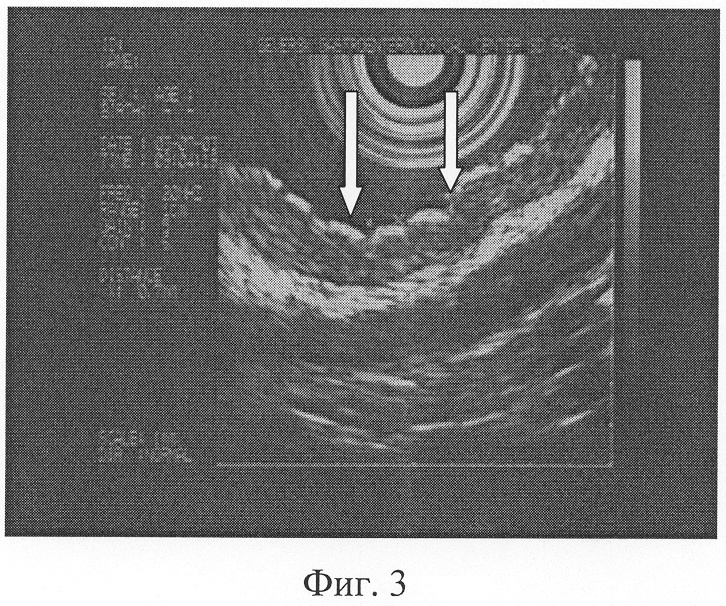

При типичном расположении складок, ширина которых в теле и антральном отделе желудка от 3 до 6 мм, по большой кривизне, в своде и синусе до 10 мм (Фиг.2), соотношении минимальной к максимальной высот желудочной складки от подслизистого слоя, приближающемся 1:2, наличии желудочных полей правильной овальной формы диаметром 1-3 мм (Фиг.3) определяют норму.

В результате проведенного исследования установлено, что пищевод свободно проходим. Слизистая пищевода обычной окраски. Кардия полностью смыкается. В желудке немного светлой слизи. Слизистая желудка во всех отделах розовая, блестящая, в антральном отделе желудка складки имеют типичное расположение, ширина складок в антральном отделе желудка от 3 до 6 мм, по большой кривизне складки расположены типично, ширина их не превышает 8 мм (Фиг.2). Соотношение минимальной к максимальной высоте желудочной складки от подслизистого слоя приближается 1:2. Желудочные поля имеют правильную овальную форму диаметром 1-3 мм (Фиг.3). Привратник сомкнут, проходим. Патологии со стороны двенадцатиперстной кишки нет. Заключение: Органической патологии не выявлено.

Фиг.2. Пациент К. 18 л. Эндоскопическая гастросонография. Типичное расположение складок желудка (обозначены стрелками), ширина которых в теле и антральном отделе от 3 до 6 мм, по большой кривизне, в своде и синусе – 8 мм. Соотношение минимальной к максимальной высоте желудочной складки от подслизистого слоя 1:2. Структура стенки желудка по слоям сохранена.

Фиг.3. Пациент К. 18 л. Эндоскопическая гастросонография. Желудочные поля (обозначены стрелками) правильной овальной формы диаметром 1-3 мм.